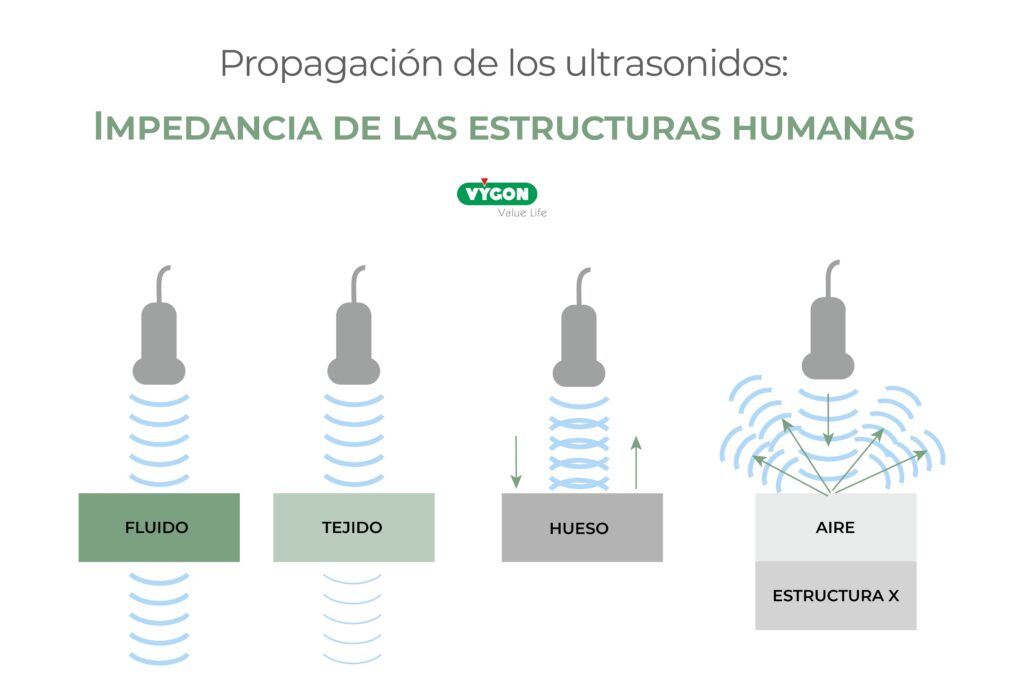

Impedancia de los tejidos

El ultrasonido, al atravesar el cuerpo, va a encontrarse con diferentes materiales (piel, grasa, músculo, sangres, hueso…) que van a ejercer una diferente resistencia a que se propague. Esta resistencia la llamaremos impedancia. La impedancia depende de la densidad del tejido.

La impedancia de cada material será diferente por sus diferentes densidades pero, a grandes rasgos, los sólidos (en especial los metales, como el calcio) ofrecen una resistencia más grande que los líquidos (sangre, orina) al paso del ultrasonido por su mayor densidad. El gas tiene un comportamiento particular, de forma que, a pesar de tener una impedancia muy baja (muy baja densidad), al no tratarse de un medio acuoso, transmite muy mal el ultrasonido.

La zona de unión entre dos tejidos o materiales con diferente impedancia la llamaremos interfase.

En ecografía, podemos distinguir las estructuras del cuerpo siempre que sean de impedancias diferentes (es decir, que exista una interfase entre ellas).

Las cualidades de las interfases influyen en cómo se comporta la onda del ultrasonido al atravesarlas. El comportamiento del ultrasonido al atravesar las interfases puede ser de las siguientes formas.

Atenuación

El ultrasonido atraviesa un medio y va perdiendo energía. Esto hace que pierda amplitud y que los ecos que produzca sean cada vez más tenues.

Absorción

Esa energía que pierde el ultrasonido al atravesar el tejido se convierte en calor, imperceptible para el paciente (excepto en la retina, donde existe un riesgo teórico de lesión para el tejido, el ultrasonido se considera inocuo para el cuerpo humano).

Reflexión

Si el ultrasonido atraviesa una interfase fina y amplia, con densidades diferentes, se reflejará en su mayoría, produciendo un eco de gran intensidad, como puede ocurrir al encontrar la interfase entre músculo y hueso.

En la imagen siguiente, se puede apreciar el fémur de un paciente. El ultrasonido llega hasta la interfase del hueso (muy denso) con el tejido circundante (muy poco denso) y se refleja con una intensidad alta (y por eso se muestra más “blanco” en la pantalla, como luego veremos).

Sin embargo, si atraviesa una interfase menos definida, en la que las densidades son similares, se dispersará en muchas direcciones diferentes, produciendo un eco de baja intensidad (que se representarán más “grises” en la pantalla), como ocurre al atravesar el parénquima hepático, donde las interfases son de densidad muy similar.

Refracción

Si el ultrasonido atraviesa dos medios con una gran diferencia en su velocidad de propagación (por ejemplo, aire y pleura), la onda cambiará de dirección y se producirá refracción. Además de ese cambio de dirección, se producirán reflejos de esa nueva dirección que se representarán en la pantalla en lugares diferentes de su origen.